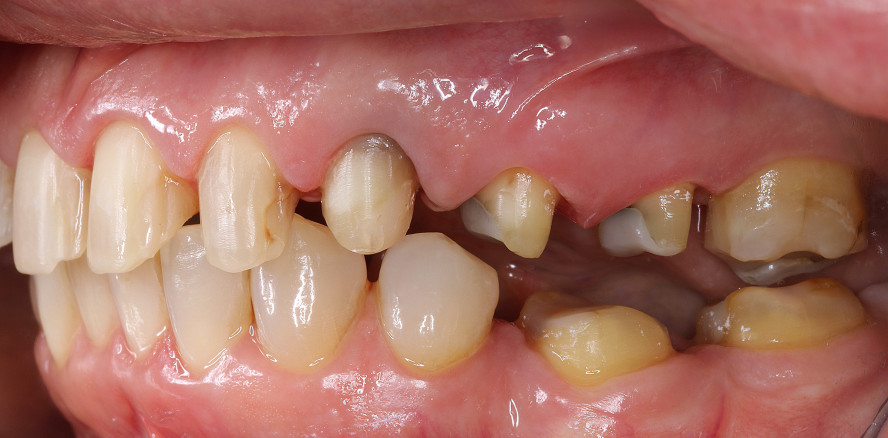

Die 66-jährige Patientin stellte sich in der Poliklinik für Zahnärztliche Prothetik der Uniklinik Köln mit dem Behandlungswunsch nach einer ästhetischen Verjüngung ihrer Frontzahnästhetik und der Wiederherstellung ihres ehemaligen harmonischen Lächelns vor. Der vorhandene festsitzende Zahnersatz war bereits 30 Jahre alt. Insbesondere ihre verfärbten freiliegenden insuffizienten Kronenränder und das Keramikchipping störten sie optisch. Der Frontzahnbereich des Oberkiefers wies multiple Kompositrestaurationen an den bukkalen and approximalen Flächen auf, die zu ungleichmäßigem Farbverlauf und Kontaktpunkten führten. Zahn 17 war alio loco durch ein LZPV versorgt, von Zahn 13 auf 16 trug die Patientin eine insuffiziente VMK-Brücke. 23 wies zwar eine regelrechte Wurzelfüllung, jedoch eine intrinsische Verfärbung auf, die trotz Walking-Bleach zu keinem zufriedenstellenden Ergebnis geführt hatte. Die Zähne 24, 25, 36, 37, 46, 47 wiesen ebenfalls insuffiziente Kronen auf. Parodontal präsentierten sich die Zähne der Patientin stabil, ohne Lockerungsgrade mit unauffälligem PSI (0/0/1/1/1/1). Die Frontzähne im Unterkiefer zeigten eine leichte Inklinationsabweichung mit interdentalen Überlappungen, charakteristisch für einen dentalen Engstand. Es gab keine klinischen Hinweise auf Parafunktionen oder einen Verlust der vertikalen Dimension, jedoch waren altersbedingte Schlifffacetten auf den Unterkieferfrontzähnen erkennbar. Abgesehen von dem endodontisch behandelten Zahn 23 waren alle Zähne vital. Zudem pflegte die Patientin eine gute häusliche Mundhygiene.